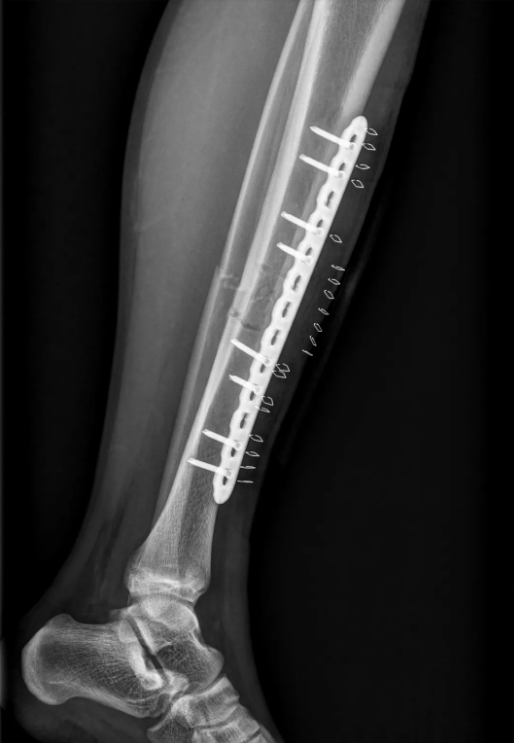

考虑到患儿正处于生长发育关键期,团队最终决定采用"微创经皮钢板内固定术",该技术能通过微小切口完成精准复位与固定,最大限度保护骨骺,避免影响未来骨骼生长。

术中,陈毅荣教授凭借精湛的技术,通过数个约1厘米的切口完成精准复位与固定,团队成员密切配合,手术过程流畅,出血少、创伤小、耗时短。术后第一天,患儿即在医护人员指导下开始早期功能锻炼。